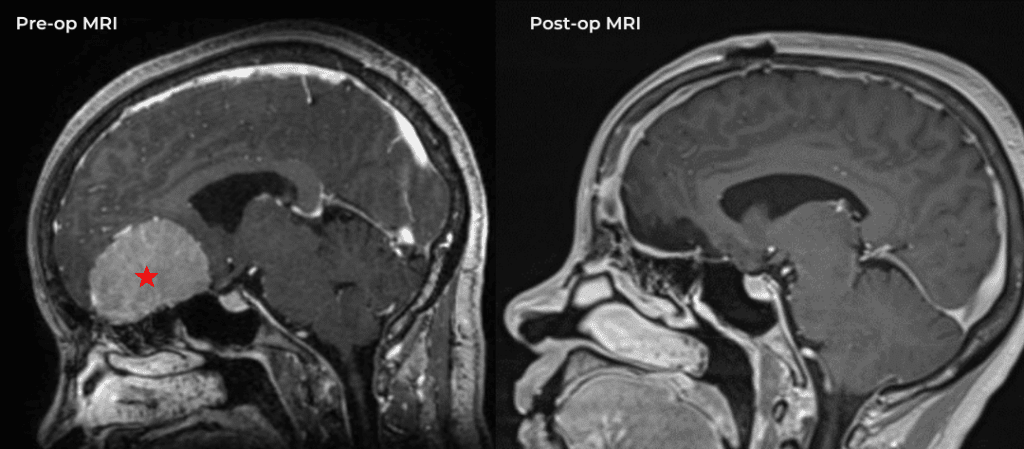

Cerebellar Hemangioblastoma

Author: Michael Brisman M.D., F.A.C.S., Read More!